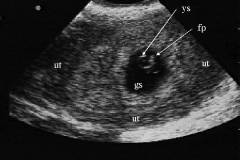

Трансвагинальное УЗИ позволяет определить беременность через 3 недели после овуляции или в течение 5 недель после последней менструации. Этот метод широко используется в отделениях скорой помощи благодаря высокой чувствительности и специфичности.

УЗИ помогает установить наличие маточной беременности, что в большинстве случаев исключает внематочную беременность (случаи одновременного развития нормальной и внематочной беременности крайне редки). Абсолютным признаком маточной беременности считается обнаружение гестационного мешка, желточного мешка и эмбриона в маточной полости.